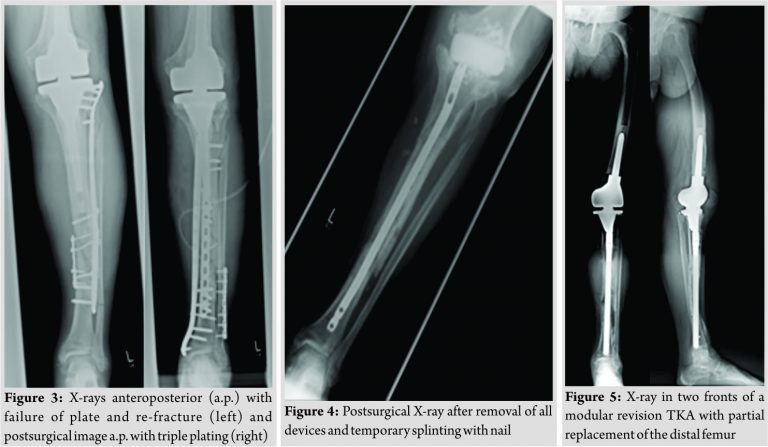

Inpatient care consisted of mobilization with two crutches and a partial weight bearing (20 kg). Microbiological examination of the initial joint puncture and all samples taking during the operation was negative. The patient was discharged with unremarkable wound conditions and normal blood counts. The patient was readmitted with persistent pain and serous secretion from a necrotic area of the distal wound 3months after discharge. Radiological examination showed a delayed union of the fracture. Immobilization in a cast and local resection of the necrosis could not prevent wound worsening within 1month. Therefore, revision surgery of the wound with a deep debridement had to be performed. Due to the missing wound consolidation, soft tissue debridement was performed in two more surgeries. The first procedure was completed with an extensive cleansing, insertion of a gentamicin-impregnated sponge, and an occlusive vacuum bandage. Antibiotic therapy was accomplished with a combination of cefuroxime (3 × 1.5 g i.v., Fresenius Kabi Austria GmbH, Graz, Austria) and clindamycin (2 × 600 mg, MIP Pharma GmbH, Blieskastel, Germany). This therapy was given in accordance with the spectrum of resistance of a multi-sensitive Staphylococcus aureus and Enterobacter cloacae (wound sample) and S. aureus, Finegoldia magna, and Corynebacterium xerosis (fracture site samples). As there was no tendency toward healing, a further surgery with new lateral and medial plating was performed. The distal wound lesion was covered with a MESH graft. Post surgical therapy included mobilization with full weight bearing. In addition, osteoanabolic therapy with Teriparatide (250 µg/ml, Lilly Germany GmbH, Bad Homburg) to improve fracture healing was applied. Antibiotic treatment was continued for 6 weeks. Histological examination confirmed an underlying chronic bone infection and the nonunion. The blood counts were normal when the patient was discharged after 27 days. 2 weeks after hospital discharge, the patient reported a sudden, atraumatic pain with immobilization. X-rays documented a fracture dislocation with the failure of the medial and lateral device and, in addition to these findings, a new distal fracture of the fibula (Fig. 3). There were no signs of consolidation at the former fracture site, and revision surgery was necessary. With the exception of two broken screw bodies, all devices were removed. A triple-plate reosteosynthesis was performed, including a 14-hole inverse LISS plate on the medial side, a 12-hole limited contact dynamic compression (LCDC) plate at the dorsal tibia aspect, and a 7-hole reconstruction plate at the new distal fibula fracture (all devices, Synthes GmBH, Umkirchbei Freiburg, Germany, Fig. 3). The nonunion was resected,and the lesion was filled with an equilateral autologous spongiosa graft of the femur taken by a reamer-irrigator-aspirator system. A multidrug-resistant Staphylococcus epidermidis (MRSE) was isolated from the microbiological samples. Since the MRSE had also been isolated during prior surgeries, it was considered a major pathogen; therefore, antibiotic treatment with cefuroxime and clindamycin was changed to vancomycin (2 × 1 g, MIP Pharma GmbH, Blieskastel, Germany) and rifampicin (2 x 600 mg, Riemser Pharma GmbH, Greifswald, Germany). The patient was discharged with an oral combination of linezolid (2 × 600 mg, MIP Pharma GmbH, Blieskastel, Germany) and rifampicin (2 × 600 mg, Riemser Pharma GmbH, Greifswald, Germany) for additional 4weeks. Blood values were taken frequently, revealing normal WBC counts and regressive CRP values. A follow-up was planned at our outpatient clinic at the end of the period of unloaded mobilization 8weeks after surgery. The initial follow-up and subjective outcome were satisfactory at 8weeks postoperatively. There was no evidence of a persistent infection. The patient had completed 2months of mobilization without weight bearing and had started partial weight bearing without any problems a few days before. Therefore, slowly increasing weight bearing to improve inpatient rehabilitation and functional outcome of the affected limb was recommended. The patient was readmitted from rehabilitation to our department in January 2015 due to a progression of knee pain and moderately elevated paraclinical values of infection. Examination at admission showed normal wounds at the fracture site, but at the knee, the skin was irritated and swollen. X-rays showed a small amount of new bone formation at the medial and lateral side of the former tibial fracture, but a fracture union was still not present. A knee puncture was performed, and the microbiological assessment showed a known MRSE, previously of the fracture site, now with a limited spectrum of sensitivity. A bone and leukocyte scintigraphy showed a persistent (infectious) nonunion and aseptic loosening of the TKA due to ascending infection. With the additional septic focus, there was a need for complete removal of all implants. Therefore, a two-stage implant change was planned. After removal of all implants, a deep debridement was performed,and a hand-formed bone cement knee spacer including antibiotics (Copal G+C 1 × 40 mg, Heraeus Medical GmbH, Wehrheim, Germany) was implanted. Microbiological and histological samples taken during surgery confirmed the chronic bone infection and septic TKA. An antibiotic treatment was started perioperatively and was given for 6weeks with a combination of vancomycin (2 × 1 g, MIP Pharma GmbH, Blieskastel, Germany) and rifampicin (2 × 600 mg, Riemser Pharma GmbH, Greifswald, Germany) followed by an oral mono-therapy with linezolid (2 × 600 mg, PHARMACIA GmbH, Karlsruhe, Germany). The mobilization was performed with full weight bearing using an individual constructed lower limb load-relieving orthosis by Allgöwer. After an antibiotic-free interval of 2 weeks, the patient was admitted for a diagnostic joint puncture. However, the knee puncture again showed purulent synovial fluid with the isolation of the prior known MRSE. The remaining broken screws and a bone abscess close to the former nonunion was removed within revision surgery. A tibial nail (T2, 315 × 10 mm, Stryker Trauma GmbH, Schönkirchen, Germany) was used for temporary intramedullary splinting and to provide further consolidation of the circumferential callus bone. Furthermore, a new bone cement spacer (Palacos R+G, 2× 40 mg, Heraeus Medical GmbH, Wehrheim, Germany) with two additional antibiotic-impregnated chains (2 × 30, Biomet Deutschland GmbH, Berlin, Germany) was implanted (Fig. 4). MRSE was ascertained everywhere except for the distal femur. In accordance with the pathogen’s spectrum of resistance, a new 6-week course of therapy with vancomycin (2 × 1 g, MIP Pharma GmbH, Blieskastel, Germany) was begun and switched to oraltherapy with linezolid (2 × 600 mg, PHARMACIA GmbH, Karlsruhe, Germany) only. The previous mobilization using the orthesis was continued. In August 2015, a puncture of the knee joint after an antibiotic-free interval showed no pathogens. Clinical examination was without any signs of persistent infection. X-rays showed only a partial consolidation of the fracture at the tibia, but the fibula was consolidated. Therefore, reimplantation of a special revision TKA, also addressing the tibial fracture was scheduled. Revision surgery included removing the nail and all other foreign bodies and an extensive debridement with reaming of the intramedullary cavity of the tibia. The surgery was completed by a partial replacement of the distal femur due to bone loss and a modular revision TKA was implanted (Mega C, modular tibia with a 14/280 mm cementless tibia stem, modular femur condyle with a 16/100 mm cemented stem, Waldemar Link GmbH and Co. KG, Hamburg, Germany; Fig. 5). The tibial fracture site was splinted stable with the long cementless stem by the means of a press fit. Intraoperative range of motion of the knee joint was extension/flexion of 0/0/100. The patient underwent full weight bearing using two crutches and patient’s orthosis for 8weeks postoperatively. Post-operative X-rays showed no malalignment of the TKA and good fracture stabilization by the tibial stem. Laboratory counts and infectious values normalized, and there was a remarkable improvement in the patient’s quality of life. A new rehabilitation was scheduled after the inpatient time of 3weeks. The patient was discharged with an active ROM of 90° in flexion. He was able to exercise on an even track for more than 20 min. The patient underwent 4months of follow-up after successfully completing rehabilitation. The patient was able to walk under full weight bearing with the aid of two crutches. Occasionally, the orthosis is carried for long distances. He reported an intermittent pain at the superficial goose’s foot in cases of higher stress. There was a temporary relief after a local anesthetic infiltration, but the pain, in general, was described as moderate. All wounds were dry and without any signs of infection. The active range of motion was tested with flexion of 0/0/90°. The patient was seen for the last follow-up 15 months after revision TKA with only moderate pain at the medial knee site. Mobilization was performed with the use of one crutch, and knee flexion is limited to 80°, which is described as acceptable for patient’s daily activities. The patient is confident with the functional outcome and quality of life.